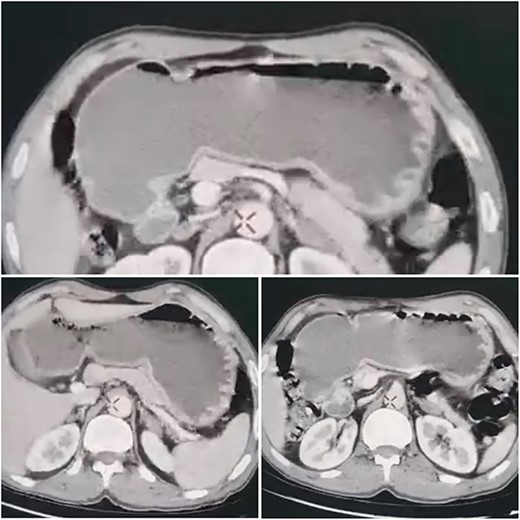

A 51-year-old patient with no significant medical history. He was admitted to the emergency department with abdominal distension, persistent vomiting, intolerance to solid foods, he could consume only small amounts of liquid. Clinical examination of the abdomen revealed diffuse tenderness in all quadrants, accompanied by severe abdominal distension. Prior to his consultation at our institution, he had undergone oesophagogastroduodenoscopy, revealing a dilated stomach and narrowing of the pyloric ring. Biopsies revealed the presence of H. pylori and S. ventriculi. (Fig. 1). He was put on conservative treatment for a duration of ~4 weeks, but no significant improvement was noted. On admission to our clinic, he underwent a computed tomography (CT) scan of the abdomen (Fig. 2), which revealed marked dilatation of the stomach, as well as an upright arrangement of the entire jejunal coves, suggesting the presence of a high occlusion due to a right anterior para-duodenal internal hernia. While a more comprehensive non-operative management approach could have been contemplated in the absence of hernia-related concerns, the clinical deterioration and the refractory nature of symptoms to medical therapy served to underscore the appropriateness of the surgical approach. During surgery, the hypothesis of a para-duodenal internal hernia was ruled out after a duodeno-pancreatic detachment using the KOCHER maneuver, thus facilitating exposure of the entire duodenum and also allowing individualization of the transition zone located at the level of the pylorus (Fig. 3), thus justifying the performance of gastroenteric anastomosis (Fig. 4). Post-operatively, the diet was progressively advanced and well tolerated. On discharge, the patient was in satisfactory condition.

CT scan of the abdomen, which revealed marked dilatation of the stomach.